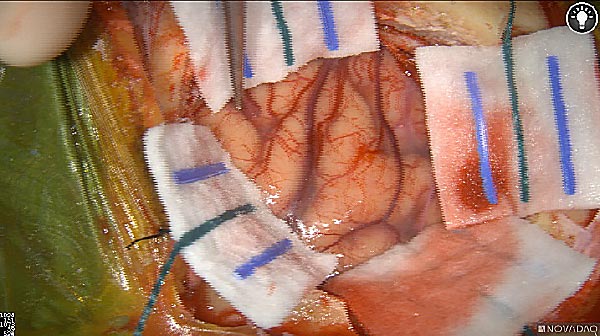

Intraoperative fluorescence imaging of the pancreas part that contains tumor

The tumor area light up fluorescently and so does a lymph node (LN; red circle) that is located on top of the tumor area. We can also see some lymphatic ducts (green circle).

After removal of the pancreas tumor fluorescence imaging was performed to check that there was no residual fluorescence left in the wound bed. A little bit of background fluorescence was found in the intestine.